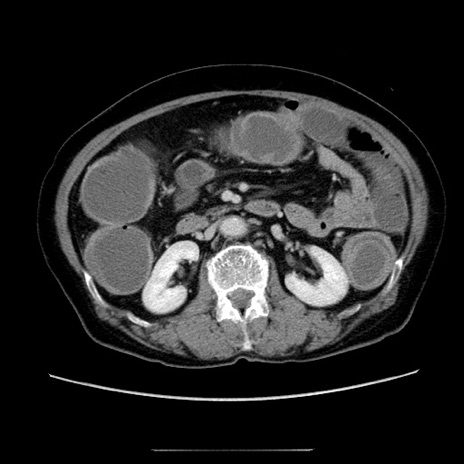

症例5(横断像)

【症例】70歳代女性

【主訴】お腹が張る

【現病歴】1週間くらい前から腹部膨満の自覚あり。昨日夜から増悪したため、本日救急外来受診。

【身体所見】意識清明、BT 36.5℃、BP 165/106mmHg、HR 80bpm、SpO2 98%、腹部:膨満、軟、自発痛・圧痛なし、触診にて不快感あり、腸蠕動音:減弱

【データ】WBC 12600、CRP 1.04